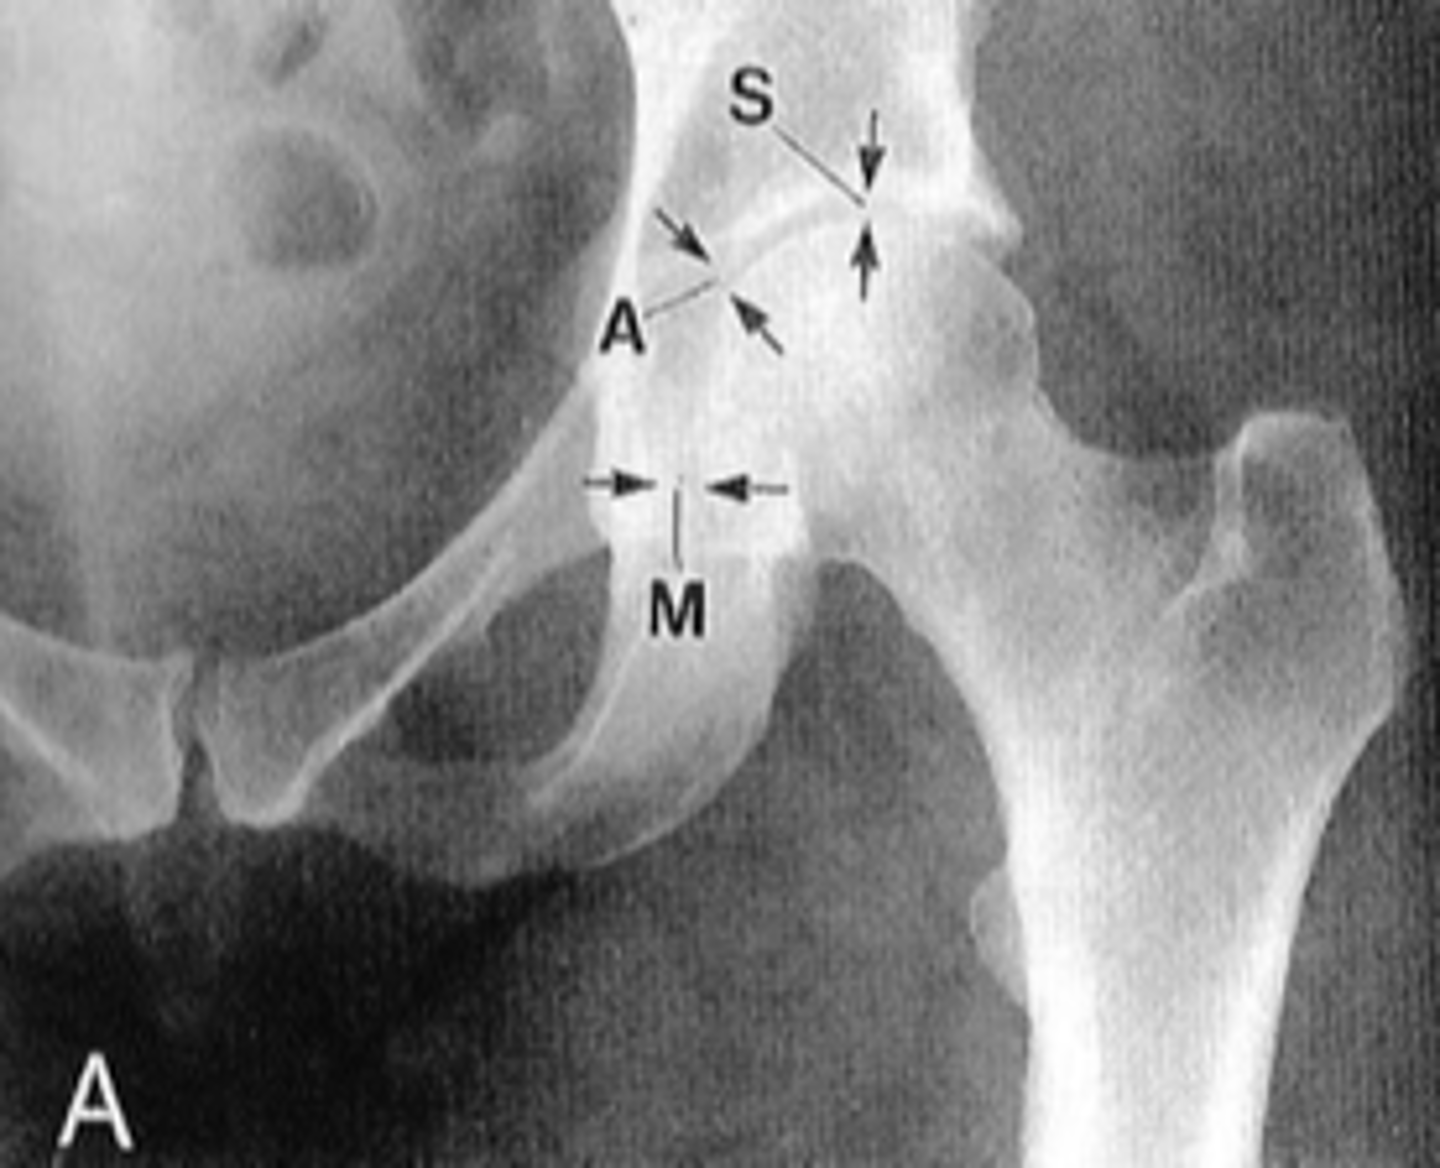

Pubic symphysis

ID 1

<p>ID 1</p>

Left femoroacetabular joint

ID 2 (joint)

<p>ID 2 (joint)</p>

Left posterior sacroiliac joint

ID 3 (joint)

<p>ID 3 (joint)</p>

Left anterior sacroiliac joint

ID 4 (joint)

<p>ID 4 (joint)</p>

Kohler's teardrop distance

ID measurement line

<p>ID measurement line</p>

- AP pelvis

- AP hip

What views are needed to see Kohler's teardrop distance?

- Medial margin of femoral head

- Lateral border of teardrop

Kohler's teardrop distance landmarks

6-11 mm

Normal Kohler's teardrop distance measurement

<p>Normal Kohler's teardrop distance measurement</p>

2 mm

The normal Kohler's teardrop distance is 6-11 mm, and there should be no greater than a _____ difference when comparing to the contralateral side

<p>The normal Kohler's teardrop distance is 6-11 mm, and there should be no greater than a _____ difference when comparing to the contralateral side</p>

Hip joint effusion

Clinical significance of an enlarged Kohler's teardrop distance

<p>Clinical significance of an enlarged Kohler's teardrop distance</p>

Waldenstrom's sign

What sign indicates an enlarged Kohler's teardrop distance?

- Accentutation of the normal limits

<p>What sign indicates an enlarged Kohler's teardrop distance?</p><p>- Accentutation of the normal limits</p>

Intracapsular swelling/joint effusion

Waldenstrom's sign is usually an indication of _____

<p>Waldenstrom's sign is usually an indication of _____</p>

Inflammatory arthritis

Clinical significance of a small Kohler's teardrop distance

<p>Clinical significance of a small Kohler's teardrop distance</p>

Hip joint space width

ID measurement

<p>ID measurement</p>

Superior, axial, medial joint spaces (SAM)

Hip joint space width landmarks

<p>Hip joint space width landmarks</p>

3-6 mm

Normal superior hip joint space width

<p>Normal superior hip joint space width</p>

3-7 mm

Normal axial hip joint space width

<p>Normal axial hip joint space width</p>

4-13 mm

Normal medial hip joint space width

<p>Normal medial hip joint space width</p>